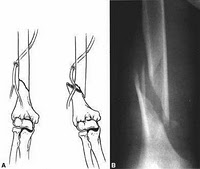

Fraktur Suprakondilar Humerus

Fraktur Interkondiler Humerus

Fraktur Batang Humerus

Fraktur Kolum Humerus

Platting

Adalah salah satu bentuk dari fiksasi

internal menggunakan plat yang terletidak sepanjang tulang dan berfungsi

sebagai jembatan yang difiksasi dengan sekrup.